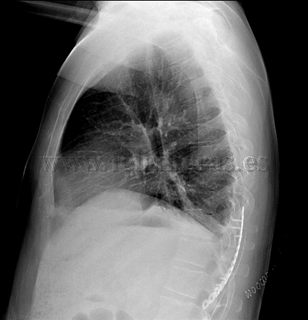

Osteosíntesis costal